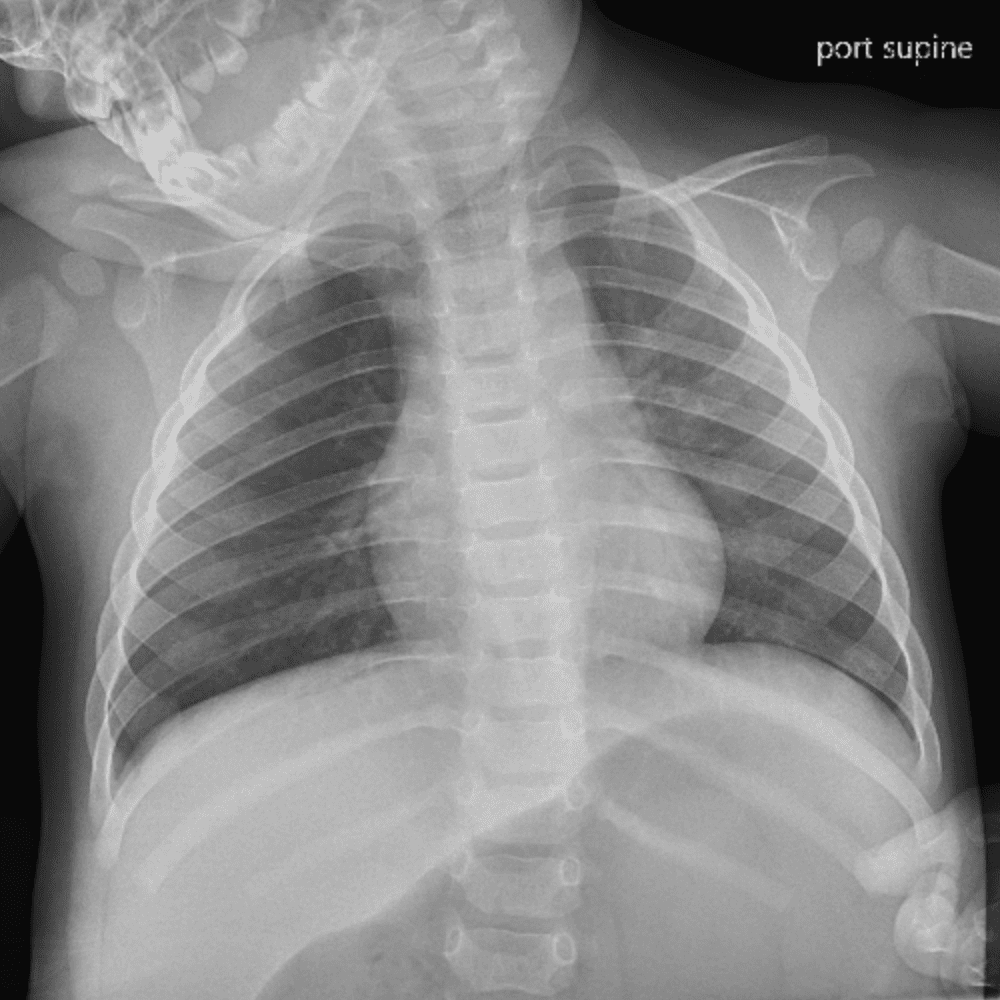

Peds Chest

Practice

Simulates call by including subtle or difficult cases and some normals.

50 cases